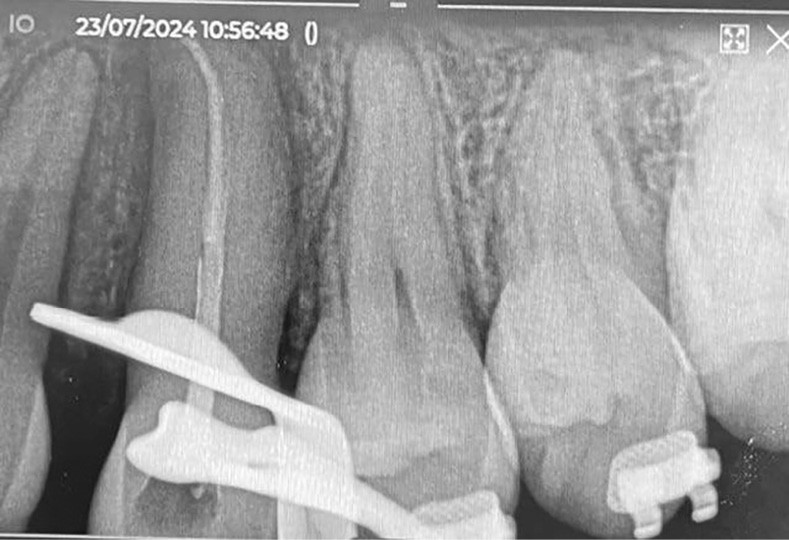

Des radiographies rétro-alvéolaires de contrôle sont effectuées au cours du traitement, il est recommandé de ne pas entreprendre de mouvement orthodontique pendant 4 mois à l’arcade maxillaire.

L’auto-transplantation de la 23 sur l’arcade, qui était en position très défavorable, et malgré un apex fermé présente de bons résultats. La radiographie rétro-alvéolaire (fig. 19) montre une intégrité de l’état radiculaire de la dent auto-transplantée. Un suivi régulier reste cependant nécessaire.